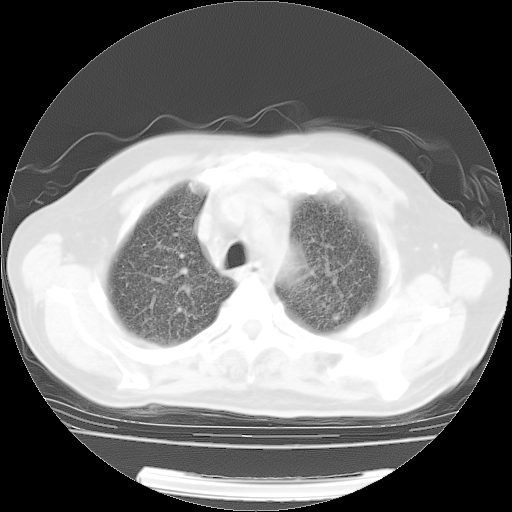

4月14日肺部CT

楼主| 发表于 2010-4-28 16:51 | 显示全部楼层

楼主| 发表于 2010-4-28 16:53 | 显示全部楼层

肺部CT平扫未见异常。